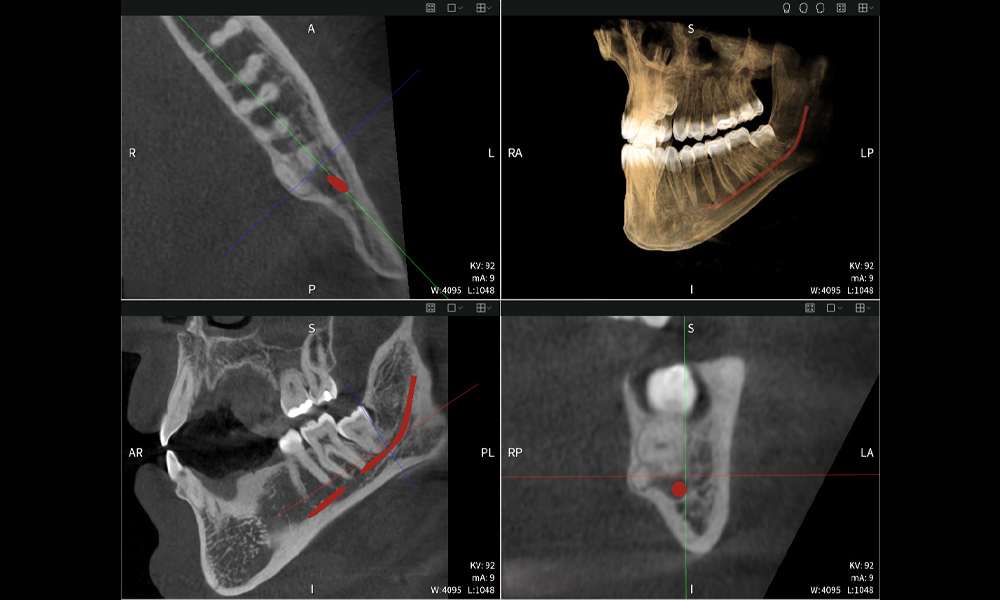

Abbildung b: Bildgebungsergebnisse von Seethrough Max vor einem schwarzen Hintergrund.

Abbildung b

Abbildung d: Bildgebungsergebnisse von Seethrough Max vor einem schwarzen Hintergrund.

Abbildung d

Abbildungen b–d zeigen verschiedene Ansichten einer 3D-Rekonstruktion des Unterkiefers und bieten eine umfassende Übersicht über die Anatomie des Unterkiefers, die Lage der Nerven im Verhältnis zu den Zähnen und ermöglichen die Beurteilung der Zahnsymmetrie und Ausrichtung.

Abbildung c: Bildgebungsergebnisse von Seethrough Max vor einem schwarzen Hintergrund.

Abbildung c

Abbildung d zeigt den bereits vorbehandelten Zahn 48, dessen Krone entfernt wurde und dessen Wurzeln nahe am Nerv belassen wurden, was das hohe Risiko einer Nervenschädigung verdeutlicht.